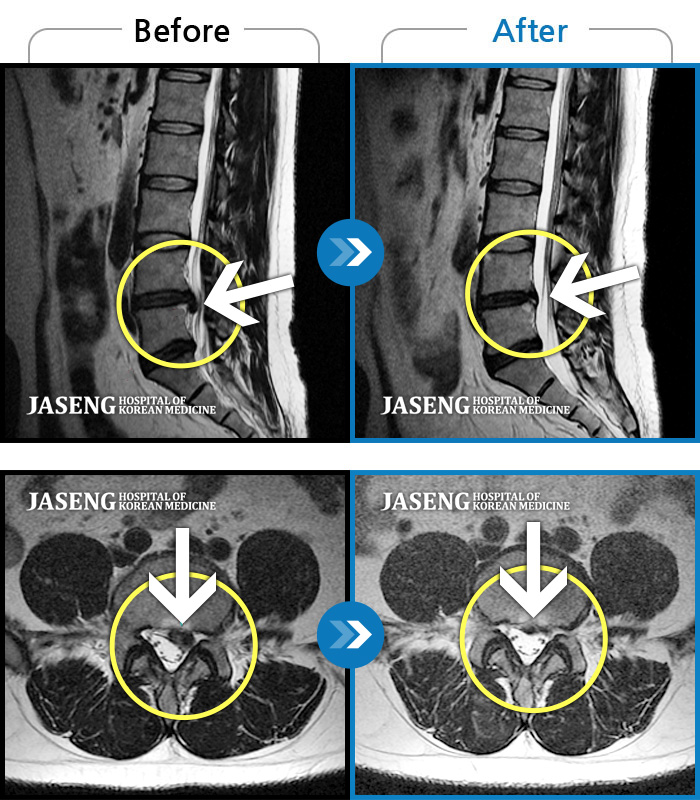

허리디스크

보라매 · 빈상은 원장

엉치에서 좌측 다리까지 통증, 저림으로 움직일 수가 없어요.

촬영시기

2024.08.03 ~ 2025.05.02

2025.12.12

조회수 118